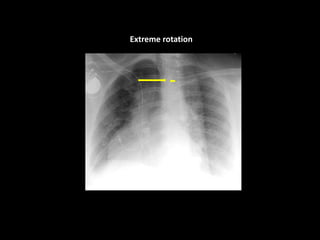

Rotation

Extreme rotation